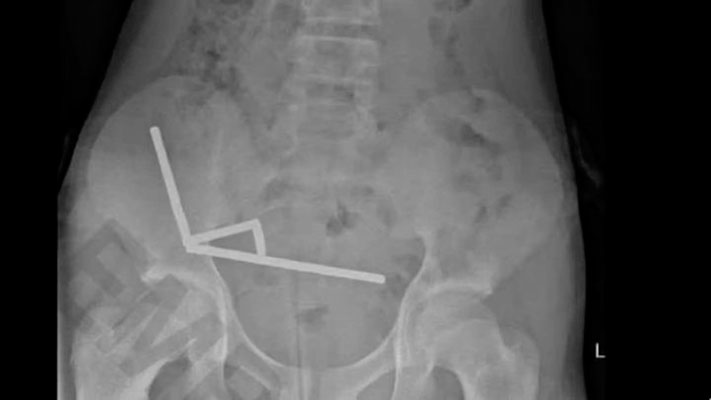

Una radiografía reveló “cadenas” de imanes en distintas secciones del intestino: cuatro agrupaciones metálicas que se habían unido a través del tejido y estaban dañando seriamente órganos vitales.

Según el estudio compartido por el New Zealand Medical Journal, aunque el niño admitió haber ingerido cerca de 100 imanes, el número real retirado durante la cirugía fue “mucho m